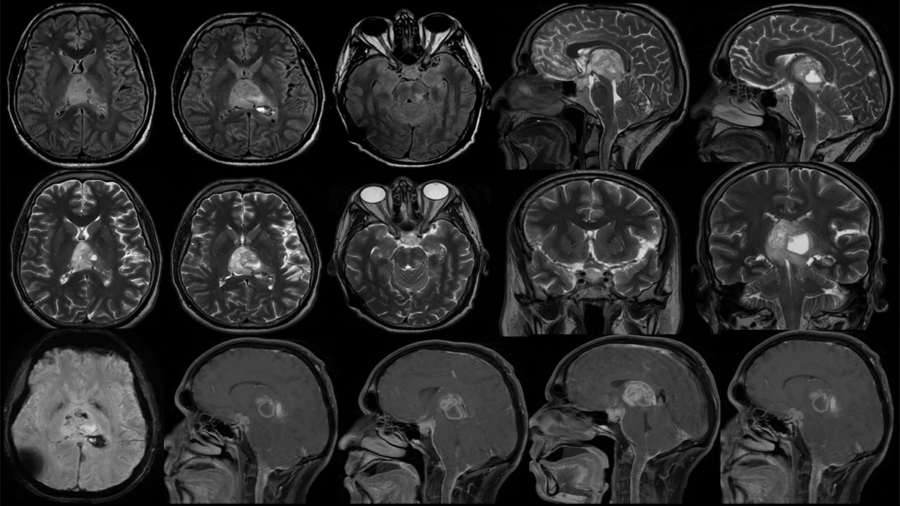

35 yr old male c/o headache, quadriparesis and blurring of vision.

December 2025 – Case 2

59-Year-old lady, a known case of chronic liver disease with portal hypertension presented with progressive left hemiparesis over three months.

December 2025 – Case 1